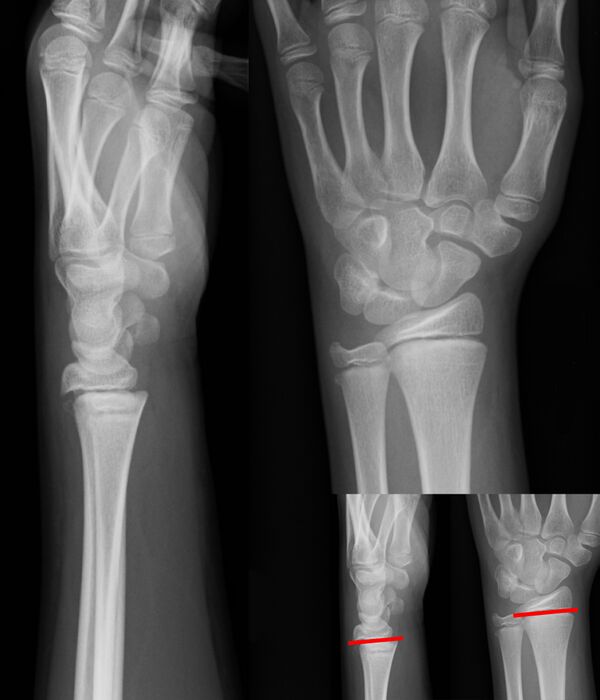

Изображения эпифизеолиза

Рентгеновские снимки переломов Салтера-Харриса с вставками где показаны линии перелома